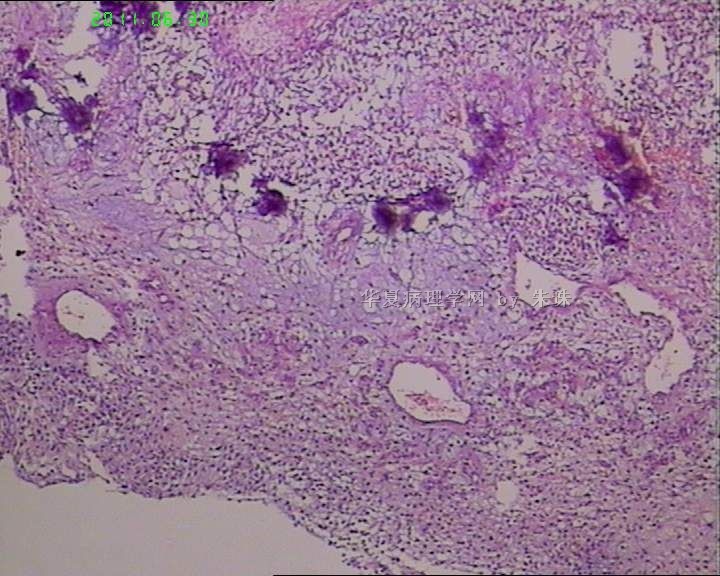

睾丸炎?

• 睾丸炎?图4

图4

首先考虑精子肉芽肿

肉芽肿性睾丸炎

精子肉芽肿